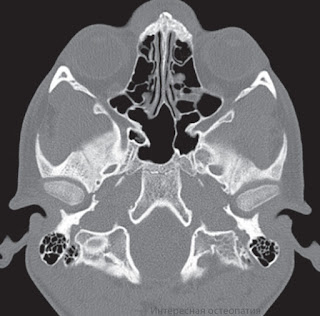

Височно-нижнечелюстной сустав (ВНЧС) (articulatio temporomandibularis), образован головкой нижней челюсти и нижнечелюстной ямкой височной кости (рис. 1-24).

Рис. 1-24. Височно-нижнечелюстной сустав ( ВНЧС).

А: 1 - скуловая дуга; 2 - скуловая кость; 3 - венечный отросток нижней челюсти; 4 - верхнечелюстная кость; 5 - второй моляр; 6 - нижняя челюсть; 7 - третий моляр; 8 - жевательная бугристость; 9 - ветвь нижней челюсти; 10 - шилонижнечелюстная связка; 11 - мыщелковый отросток нижней челюсти; 12 - передняя (наружная) часть латеральной связки височнонижнечелюстного сустава; 13 - задняя (внутренняя) часть латеральной связки височнонижнечелюстного сустава; 14 - сосцевидный отросток височной кости; 15 - наружный слуховой проход.

Б: 1 - клиновидная пазуха; 2 - латеральная пластинка крыловидного отростка клиновидной кости; 3 - крыловидноостистая связка; 4 - ость клиновидной кости; 5 - шейка нижней челюсти; 6 - клиновиднонижнечелюстная связка; 7 - шиловидный отросток височной кости; 8 - мыщелковый отросток нижней челюсти; 9 - шилонижнечелюстная связка; 10 - отверстие нижней челюсти; 11 - крыловидный крючок; 12 - крыловидная бугристость; 13 - угол нижней челюсти; 14 - челюстноподъязычная линия; 15 - моляры; 16 - премоляры; 17 - клыки; 18 - твердое нёбо; 19 - медиальная пластинка крыловидного отростка; 20 - нижняя носовая раковина; 21 - клиновид- нонёбное отверстие; 22 - средняя носовая раковина; 23 - верхняя носовая раковина; 24 - лобная пазуха

Головка нижней челюсти - валикообразное утолщение эллипсовидной формы, вытянутое в поперечном направлении. Оси, продолженные по длиннику головки, конвергируют у переднего края большого затылочного отверстия, образуя тупой угол. Спереди головки, в крыловидной ямке, прикрепляется латеральная крыловидная мышца. Задняя поверхность головки слегка выпуклая, треугольной формы, с основанием, обращенным вверх. Суставная поверхность нижнечелюстной ямки в 2-3 раза больше головки нижней челюсти. Она имеет эллипсовидную форму. Ямка делится на две части: переднюю - внутрикапсулярную и заднюю - внекапсулярную. Инконгруэнтность между головкой и ямкой выравнивается за счет суставного диска и прикрепления капсулы сустава на височной кости. Внутрикапсулярная часть суставной ямки спереди ограничена скатом суставного бугорка, сзади - каменисто-барабанной щелью. Снаружи ямка ограничена корнем скулового отростка, изнутри - угловой остью клиновидной кости. Форма нижнечелюстной ямки различна и зависит от индивидуальных факторов развития, а также характера зубной окклюзии. Выделяют две крайние формы - глубокую и плоскую.